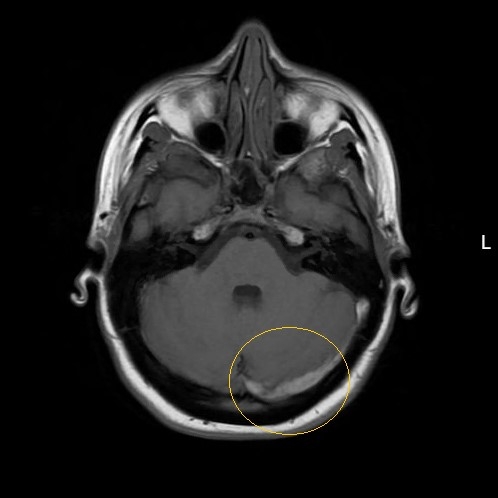

| More Than Just In Your Head: Persistent Headache In A Young Female After Low Impact Head Collision - Page #3 | |||